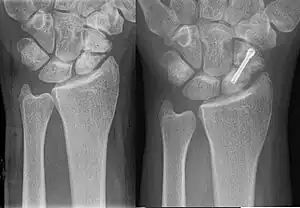

| An X-ray showing a fracture through the waist of the scaphoid | |

A subtle scaphoid fracture

A more obvious scaphoid fracture on a scaphoid view X ray

Radiolucency around a 12 days old scaphoid fracture that was initially barely visible.[11]

Fracture of the tubercle of the scaphoid bone of the wrist